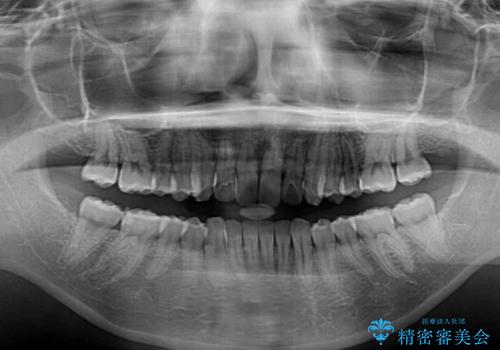

改善の期待できない口元の突出感改善を希望されたため、いたずらに治療期間が延びましたが、きっちりと仕上がりました。